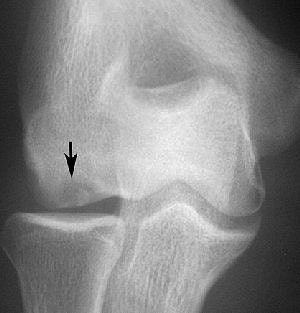

![]() |

| JOCD of the capitellum. Coronal T2-weighted image (A, above), sagittal T1-weighted image (B, middle) and coronal T1-weighted image with fat saturation (C, below) demonstrate disruption of the articular cartilage (black arrows in images figures A and C) and the crescentic subchondral signal abnormality (white arrows in figures A and C) that is typical of an osteochondritis dissecans lesion. Images courtesy of Dr. Douglas Beall. |